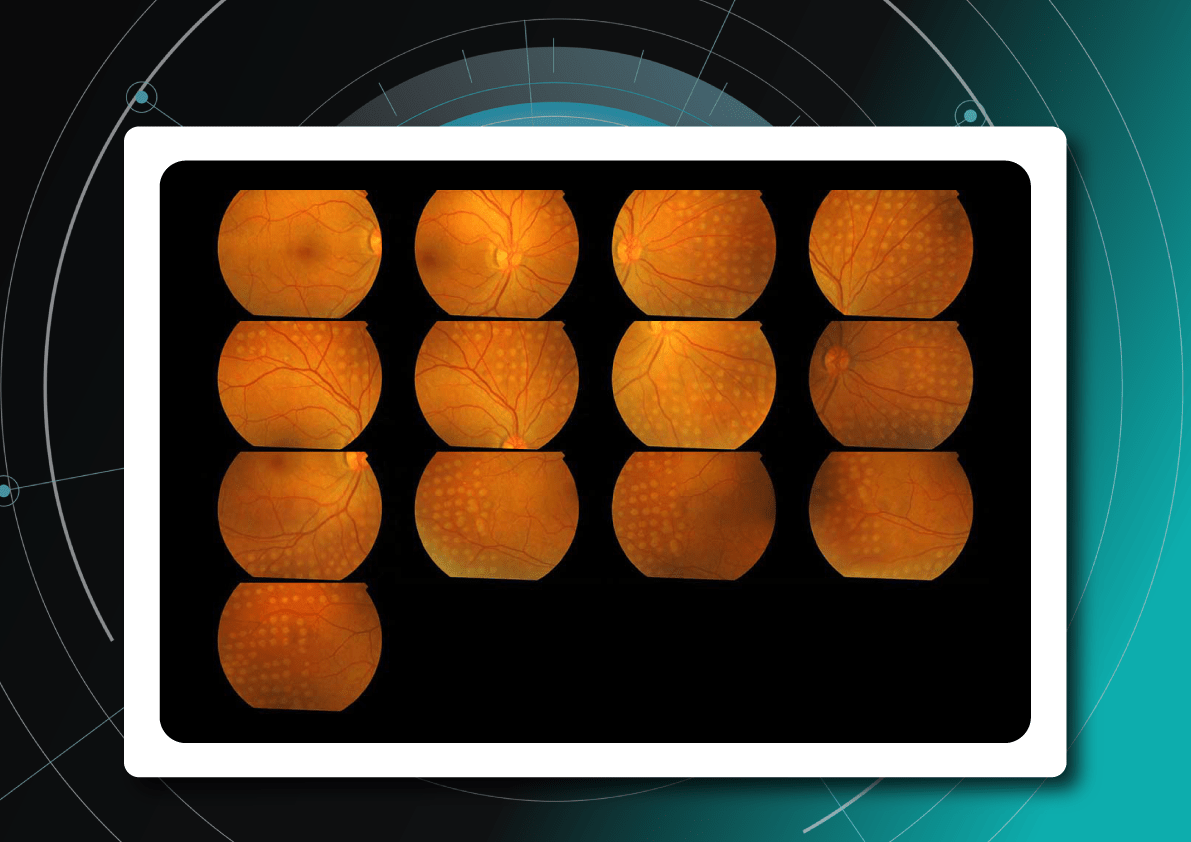

The most immediate and practical AI implementation in optometry is the analysis of medical images, such as fundus photos and OCT scans.

For instance, AI today can assess the early risk of glaucoma based on the GCC asymmetry measurements. Here is how AI-powered OCT workflow would look.